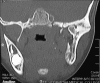

Temporomandibular joint (TMJ) ankylosis in children is one of the most complex and challenging problems managed by oral and maxillofacial surgeons. TMJ ankylosis in growing children often leads to facial deformity, difficulty in chewing and swallowing, severe malocclusion, poor oral hygiene, multiple decayed teeth, and impairment of speech. A good functional and esthetic outcome can be achieved after reconstruction with the autogenous grafts. Here, we present a case of a 9-year-old patient treated with condylectomy and ipsilateral coronoidectomy, followed by reconstruction with costochondral graft with 5 years of follow-up. During this period, the reconstructed graft remodeled into a neocondyle and also regrowth of the coronoid process. The mouth opening and facial symmetry were acceptable.